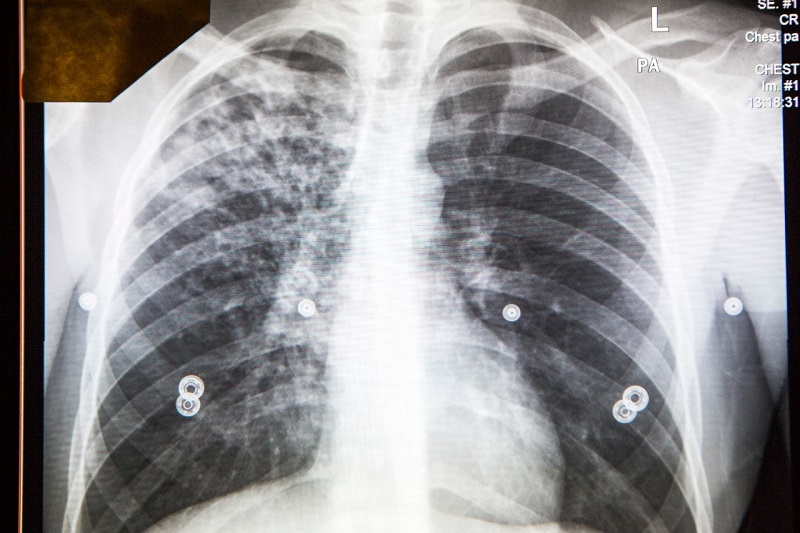

结核病是一种通过空气传播的疾病,在与感染活动性结核病的个人长期、反复和密切接触期间传播。人们在呼吸患有结核病的人呼出的空气时可能会感染结核病。如果不及时治疗,结核病可能导致严重的并发症。

结核病不会通过握手、分享食物或饮料、床单或马桶座圈传播。并非所有感染结核病细菌的人都会生病。

患有非活动性(潜伏性)结核病的人不能将其传播给他人。虽然传播的风险很低,但建议可能接触过该病毒的学生到他们的初级保健提供者、CSUSB学生健康中心或DPH进行检测。CSUSB的员工可能已经接触到这种病毒,应该去他们的初级保健提供者或DPH那里进行检测。